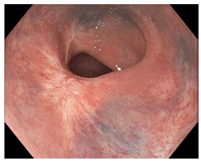

| Endoscopy | Flat white scar Telangiectasia Absence of ulcers and mucosal nodularity | Small mucosal nodules/minor mucosal irregularities Superficial ulceration Mild, persistent erythema of the scar | Visible tumor |

| Flat, white scar | ![]() | ![]() | ![]() |